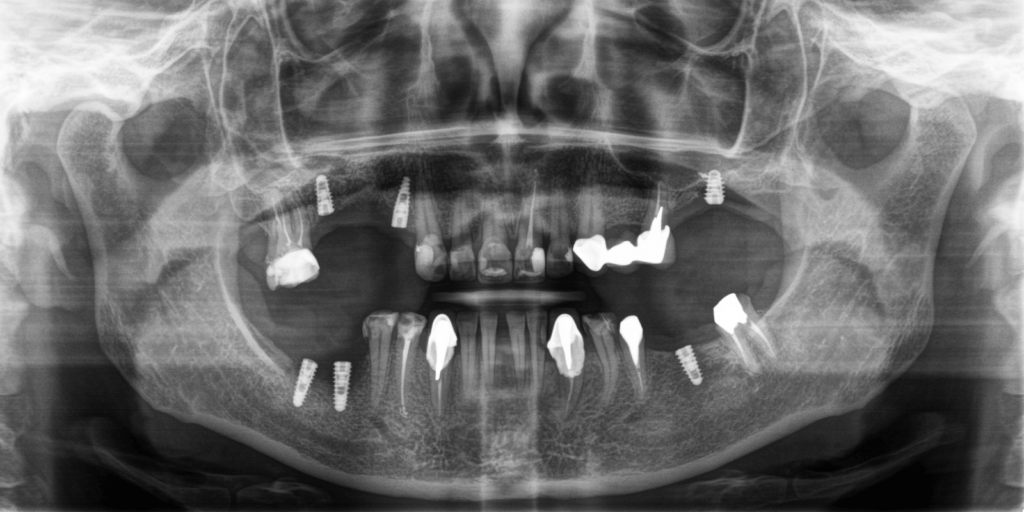

- Расколотые зубы 1.5, 1.6 (под мостовидным протезом) – удалить.

- Одновременно с удалением выполнить операцию по аугментации костной ткани.

- Отсрочено провести операцию по имплантации в области зубов 1.4 и 1.6.

- Одноэтапно установить зубные импланты в области зубов 2.6, 3.6, 4.6, 4.7.

- Ортопедическим методом поднять зубной прикус для предотвращения дальнейшего разрушения зубного ряда и с целью снятия нагрузки на суставы.

На тот момент пациентка согласилась, и наша команда приступила к лечению, которое состояло из следующих этапов: